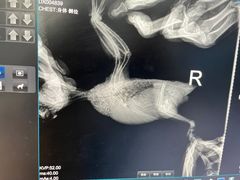

• 瑞派·关忠动物医院·异宠专科·犬猫肿瘤·皮肤专科(望京店)

• -瑞派·关忠动物医院·异宠专科·犬猫肿瘤·皮肤专科(望京店)

匿名用户 | 24-05-05